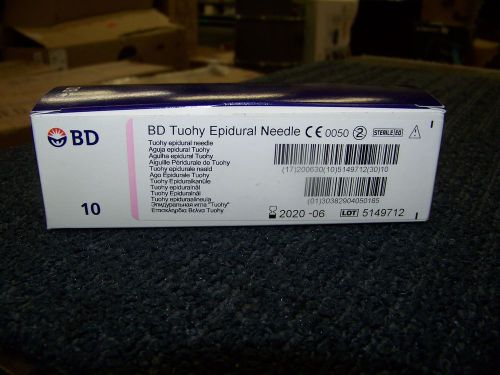

BD Tuohy Epidural Needle 18 ga. 3.50in Expires 06/2020 10 each